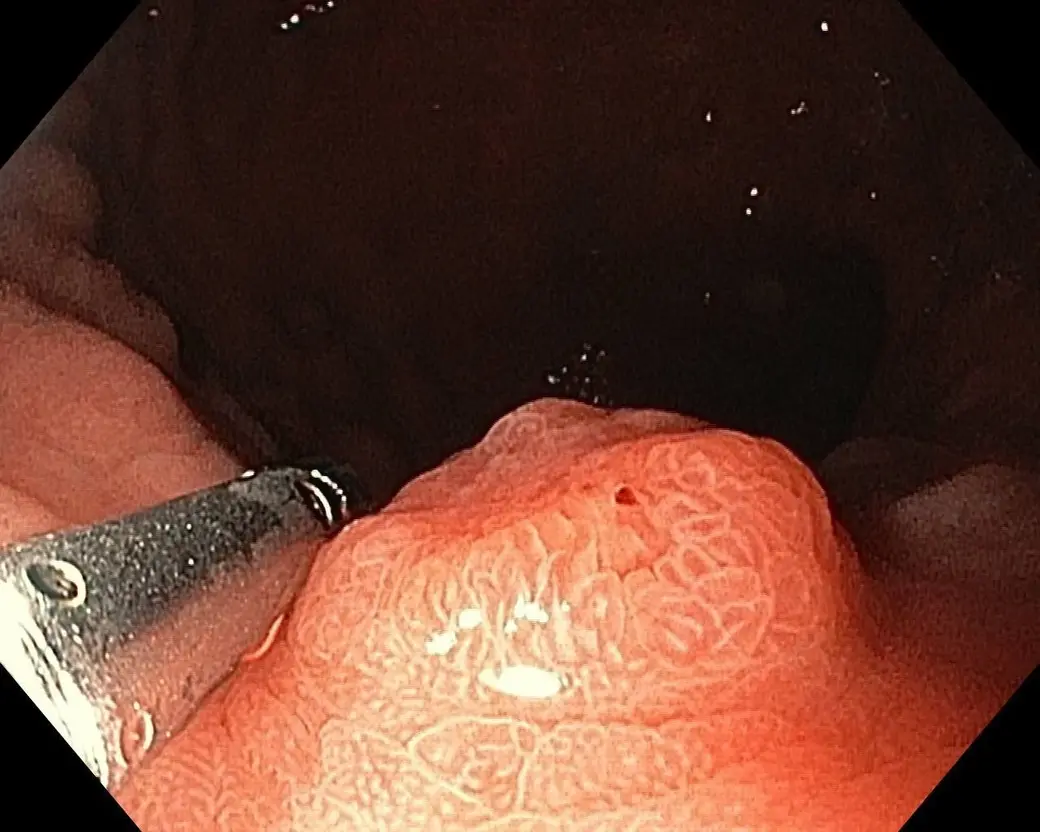

Рак не возникает сразу – сначала на стенках кишки появляется полип. При этом долгое время человека может ничего не беспокоить. Со временем полип видоизменяется, увеличивается и в конце концов может переродиться в злокачественную опухоль.

90% новообразований в кишечнике, которые мы находим, – аденома с различной степенью дисплазий. По статистике, из трехмиллиметрового полипа онкология возникает через пять-шесть лет. Если в это окно пациенту не сделают колоноскопию, вероятность возникновения рака очень высока.

Онкологические заболевания до определенных стадий также могут никак не проявляться. Постепенно раковая опухоль разрастается на всю кишку и закрывает просвет, что может вызвать запоры или даже кишечную непроходимость. Очень часто люди обращаются к врачу уже на третьей-четвертой стадии рака, когда болезнь запущена. В данном случае эндоскопист вам не сможет помочь – понадобится обширная операция по удалению опухоли. А колоноскопия предназначена прежде всего для выявления и удаления новообразований на ранних стадиях. Мы можем увидеть полипы толстой кишки даже самого маленького размера, сразу удалить их и отправить на гистологическое исследование.

Полипы мы находим примерно у 35-40 % пациентов после 40 лет. Чем старше возраст, тем, соответственно, выше эта цифра. Находим новообразования и у молодых людей 20-30 лет.

– При первичной колоноскопии мы можем удалять полипы только до 5 мм. Из каждого найденного полипа врач берет биопсию. Это абсолютно безболезненно для человека, так как в слизистой толстого кишечника нет иннервации.

Полипы больших размеров удаляем только в стационарных условиях, поскольку необходимо дальнейшее наблюдение пациента после процедуры. Как правило, это делается во время повторной колоноскопии через два-три месяца, если у пациента были обнаружены новообразования. В нашем отделении каждый день мы проводим до десяти колоноскопий в день, из них – две-три колоноскопические полипэктомии.